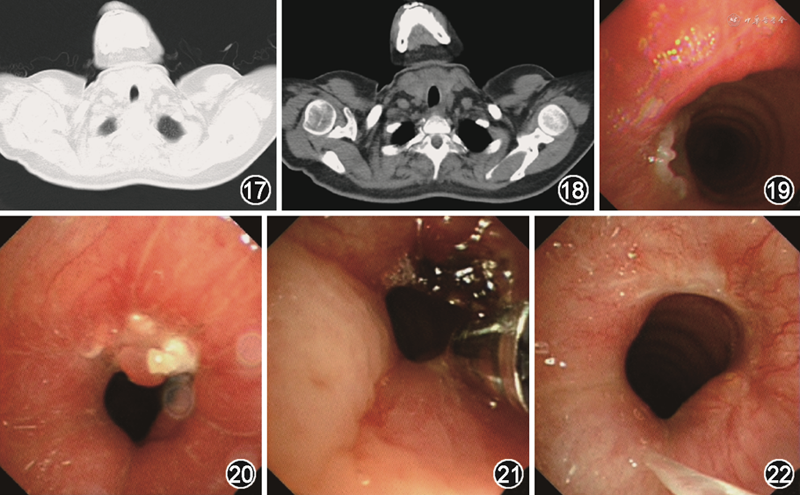

完善术前相关检查,排除手术禁忌证后,在耳鼻喉科行气管切开+经颈脓肿切开引流,术中所见:气管前壁软化、塌陷,气管第二软骨环部分坏死,气管第三软骨环软化、塌陷,气管内黏膜下囊肿样新生物,约1.5 cm×1.5 cm,内见大量浑浊黏性分泌物,左侧气管壁与周边主组织粘连重,界限欠清(图7~9)。术后病理回报为支气管黏膜坏死、化脓,软骨显示化脓性炎症(图10,11)。脓液标本革兰染色:革兰阳性杆菌菌丝,菌丝呈90°分枝,被白细胞包裹,弱抗酸染色阳性(图12),抗酸染色弱阳性。脓液分离培养见血平板干燥褶皱浅黄色菌落,直径2~3 mm,有泥土腥味(图13)。分离培养涂片革兰染色阳性杆菌菌丝,同时弱抗酸染色及抗酸染色阳性(图14, 15, 16)。因重庆地区无法行美国临床和实验室标准协会(CLSI)推荐的肉汤稀释法的药敏实验,根据临床需要,我院微生物室行K-B法药敏实验给予参考,对磺胺甲噁唑/甲氧苄啶敏感。分离培养后菌种质谱分析鉴定为巴西诺卡菌。综合患者临床表现、影像学检查、脓液革兰染色、脓液分离培养及革兰染色、菌种质谱分析鉴定结果,最终该患者确诊为巴西诺卡菌感染导致的气管脓肿。术后4 d复查胸部CT未见气管狭窄(图17,18),支气管镜检查气管壁未见脓肿及狭窄(图19)。术后1个月,患者呼吸困难再次加重,再次急诊入院,急诊行支气管镜检查,可见气管上段手术处出现肉芽,气管壁黏膜红肿,周围有黄色分泌物附着(图20),立即在镜下行氩气刀、冷冻处理(图21),术后患者呼吸困难缓解。气道介入术后1个月,患者无呼吸困难,复查支气管镜可见气管狭窄明显好转(图22)。随访3个月,无呼吸困难症状。